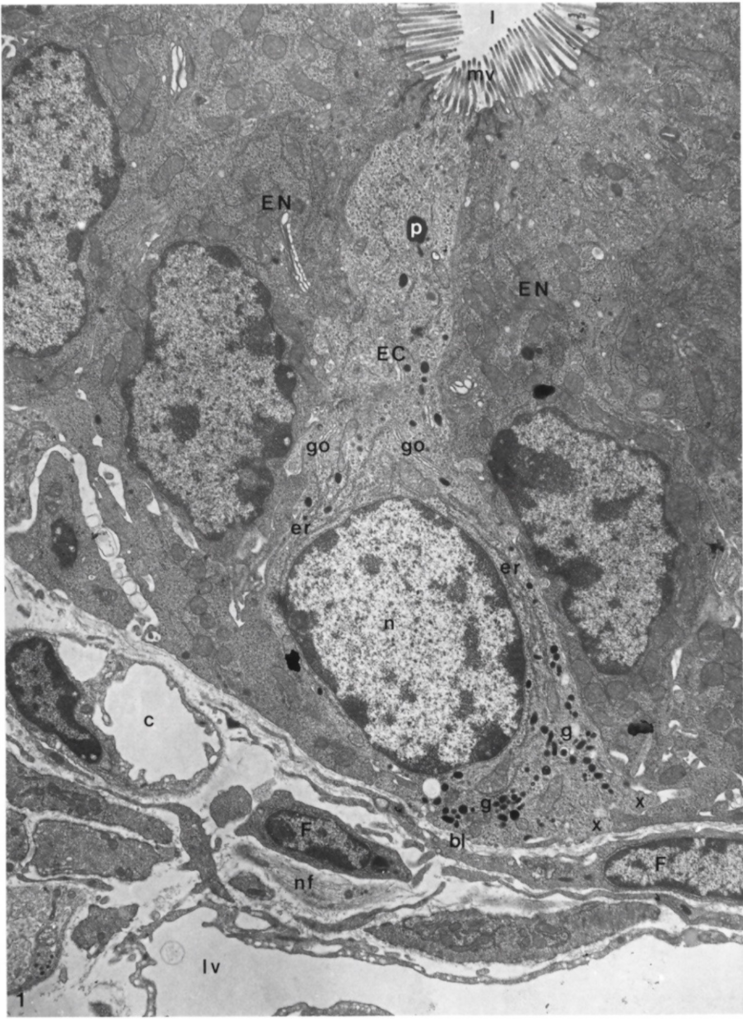

4. Ultrastructural Features of Enterochromaffin Cells and Their Bipolarity

- Wade, P.R.; Westfall, J.A. Ultrastructure of enterochromaffin cells and associated neural and vascular elements in the mouse duodenum. Cell Tissue Rev. 1985, 241, 557–563. [Google Scholar] [CrossRef] [PubMed]

- Forssmann, W.G.; Orci, L.; Pictet, R.; Renold, A.E.; Rouiller, C. The endocrine cells in the epithelium of the gastrointestinal mucosa of the rat. J. Cell Biol. 1969, 40, 692–715. [Google Scholar] [CrossRef]

- Nilsson, O.; Ahlman, H.; Gefferd, M.; Dahlström, A.; Ericson, L.E. Bipolarity of duodenal enterochromaffin cells in the rat. Cell Tissue Res. 1987, 248, 49–54. [Google Scholar] [CrossRef]